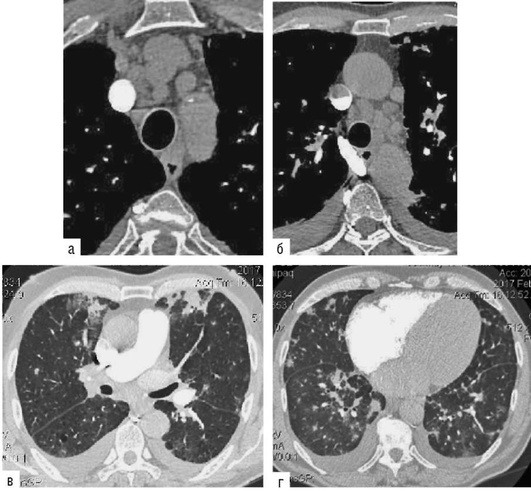

Лучевые методы исследования. Рентгенологическая картина при ЭТА зависит от стадии заболевания. В начальной фазе выявляются признаки отека интерстициальной ткани легких и распространенные мелкоочаговые затенения. При прогрессировании процесса формируются двусторонние изменения легочного рисунка по типу интерстициального фиброза, преимущественно в нижних отделах легких (рис. 2.28). В далеко зашедших случаях определяется мелко- и крупноячеистая деформация легочного рисунка. Описаны случаи, когда единственным рентгенологическим признаком болезни был односторонний плевральный выпот. Отсутствие каких-либо изменений на рентгенограммах отнюдь не исключает ЭТА. Так, при бериллиозе у 23-59% больных может выявляться умеренно выраженная двусторонняя лимфоаденопатия, а в ряде случаев - рентгенотрицательная форма бериллиоза (Dweik R.A., 2015). У 30% из 71 больных ЭТА, наблюдавшихся нами в клинике пульмонологии, в момент обследования изменений на рентгенограммах не было (Орлова Г.П., 2019). Группа больных ЭТА была обозначена условно как рентгенотрицательная группа. Уточнить диагноз помогает КТ легких, выявляющая интерстициальные изменения в легочной ткани по типу «матового стекла», усиление и деформацию легочного и сосудистого рисунка (рис. 2.29), фиброзные изменения тяжистого и звездчатого типов, на поздних стадиях - «сотовое легкое». ВРКТ выявляет «матовое стекло» и другие изменения в легочной паренхиме, которые не видны при обычном рентгенологическом исследовании. Но даже ВРКТ не всегда выявляет изменения в легочной ткани. Так, в 25% случаев гистологически подтвержденного хронического берил-лиоза легких ВРКТ была нормальной (Dweik R.A., 2013; Амосов В.И., Сперанская А.А., 2015; Amanullah S. et al., 2015).

Проведенное нами динамическое исследование КТ-паттернов у 42 больных ЭТА показало трансформацию отдельных типов интерстициальных пневмоний по мере прогрессирования патологического процесса в фиброзную НСИП или ОИП (рис. 2.30), что подтверждает объединительную концепцию интерстициальных пневмоний вне зависимости от этиологического фактора, которые являются не отдельными нозологическими формами, а стадиями течения фиброзирующего процесса в легких (Илькович М.М., Новикова Л.Н., 2018; Орлова Г.П. и др., 2019).

Исследование легочно-сердечной гемодинамики. При эходоплеркардиографии отмечается увеличение систолического давления в легочной артерии за счет повышения общего легочного сопротивления по отношению к нормальным величинам. Наличие нарушений гемодинамики малого круга кровообращения подтверждается данными сцинтиграфии легких с 99m[Tc], указывающими на диффузные нарушения перфузии разной степени выраженности. Перфузионная сцинтиграфия позволяет выявить осложнение альвеолита тромбоэмболией мелких ветвей легочной артерии. Так, при амиодарониндуцированном ЭТА в 31,1% случаев могут выявляться субплевральные участки консолидации легочной ткани, подозрительные на присоединение тромбэмболии мелких ветвей легочной артерии (Яковлева Н.С. и др., 2019). В этих случаях диагностика тромбоэмболии по данным КТ затруднена на фоне текущего альвеолита или распространенных фиброзных изменений. По нашим данным, из 16,7% больных только у 3,3% ТЭЛА была выявлена при ангиоКТ, а у 13,4% больных признаки тромбоэмболии мелких ветвей легочной артерии выявлялись при перфузионной сцинтиграфии с Тс-99-МАА (рис. 2.31).